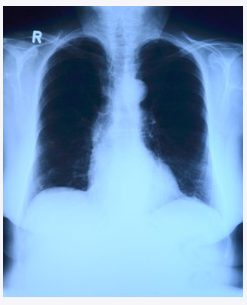

사실 폐암 초기증상이 바로 나타나면 좋겠지만 초반에 증상이 없기로 유명한 것 중 하나가 바로 폐암입니다. 그래서 사망률 또한 높을 수밖에 없는데요. 비록 미미하긴 하지만 어쨌든 폐암 초기증상이 존재하긴 하므로 이를 잘 숙지해 둘 필요성은 있습니다.

폐암 초기증상 7가지에 대해 알아보았는데요. 물론 이러한 증상이 나타난다고 해서 100% 폐암 초기증상이라고 할 수 없지만 어쨌든 의심해 볼 필요성은 있습니다.

평상시에는 없다가 어느 순간 나타나기 시작한다면 병원에 가서 진료를 받는 것은 나쁘지 않죠. 1년에 한 번씩 건강검진을 받으면 좋겠지만 살면서 그것도 쉽지가 않기 때문에 이러한 간단한 증상을 숙지해 놓는 것도 건강을 지키는데 큰 도움이 되리라 생각됩니다.